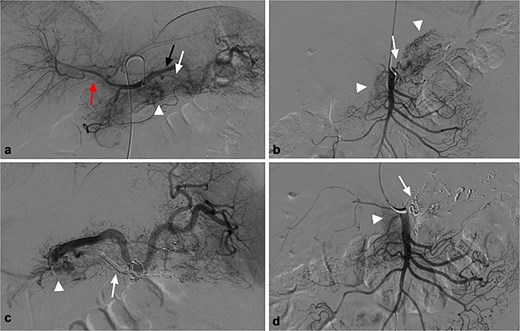

For further diagnosis and treatment, angiography and embolization under local anesthesia were agreed on. Celiac and superior mesenteric angiography through the right femoral approach confirmed PVAM which mainly originated from great pancreatic artery (Fig. 2a) and superior mesenteric artery (Fig. 2b). Selective embolization of great pancreatic artery was performed using a mixture of n-butyl-2-cyanoacrylate (NBCA) (Histoacryl; Compont, Beijing, China) and iodized oil (Poppy Ethidium, Hengrui, Jiangsu, China) combined in a 1:3 ratio. After the embolization, repeat angiography showed significant regression of the PVAM (Fig. 2c). Because selectively catheterizing the major feeding branch of superior mesenteric artery failed through the right femoral approach, embolization using the same mixture was done through the right radial approach. After the embolization, only minimal residual staining of the pancreas can be seen (Fig. 2d). The clinical outcome was good, the patient suffered mild abdominal pain for 2 days and no severe embolization-related complications, and was discharged 4 days after the procedure. Follow-up CT scan after 8 months demonstrated progressive regression of the PAVM (Fig. 3). At the time of writing this manuscript, the patient had completed 32 months of follow-up and had no recurrent AP or abdominal pain.

(a) Celiac angiography showed PVAM (white arrowhead) with numerous fine feeders mainly originating from splenic artery (black arrow) and great pancreatic artery (white arrow), as well as early portal vein opacification (red arrow). (b) Superior mesenteric angiography shows other fine feeders mainly originating from one branch of superior mesenteric (white arrow) artery with PVAM (white arrowhead). (c) Post embolization angiogram of splenic artery shows occlusion of great pancreatic artery (white arrow), and minimal residual staining of the pancreas (white arrowhead). (d) Post embolization angiogram of the supplying branch shows occlusion of the concerned artery (white arrow) and minimal residual staining of the pancreas (white arrowhead).